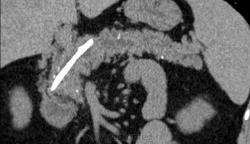

Итак пациент мужчина 34 года, в анамнезе - 16 эпизодов острого панкреатита (!). Пациенту была выполнена ЭРХПГ которая выявила наличие двух стриктур протока Вирсунга в области головки поджелудочной железы (доброкачественная стриктура Вирсунгова протока). На представленных мной изображениях определяется неоднородная структура поджелудочной железы с гиподенсными участками в области тела/хвоста и наличием паренхиматозных кальцификатов (b & c). Такая картина указывает на хронический панкреатит. В области головки визуализируется стент (a), установленный в Вирсунгов проток, с свободным концом в просвете 12-ти перстной кишки. Такое стояние стента является правильным. На данный момент, единственной адекватной терапией при доброкачественных стриктурах протока поджелудочной железы (и при некоторых опухолях исходящим из протока или обтурирующих его, когда невозможно выполнить резекцию) является эндоскопическое стентирование протока, что обеспечивает нормальный отток секрета поджелудочной в кишечник.